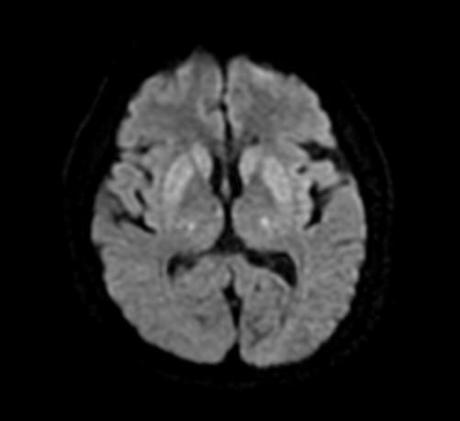

Cambios en la señal de los ganglios basales y la protuberancia, hiperintensas en Flair y con restricción en DW. Sugieren mielinolisis pontina o también llamado sind. De desmielinización osmótica, que buen caso, gracias por las imágenes

Cambios en la señal de los ganglios basales y la protuberancia, hiperintensas en Flair y con restricción en DW. Sugieren mielinolisis pontina o también llamado sind. De desmielinización osmótica, que buen caso, gracias por las imágenes

Síndrome de desmielinización osmótica con hallazgos pontinos y extrapontinos

Síndrome de desmielinización osmótica con hallazgos pontinos y extrapontinos

Mielinolisis pontina y extrapontina!

Mielinolisis pontina y extrapontina!